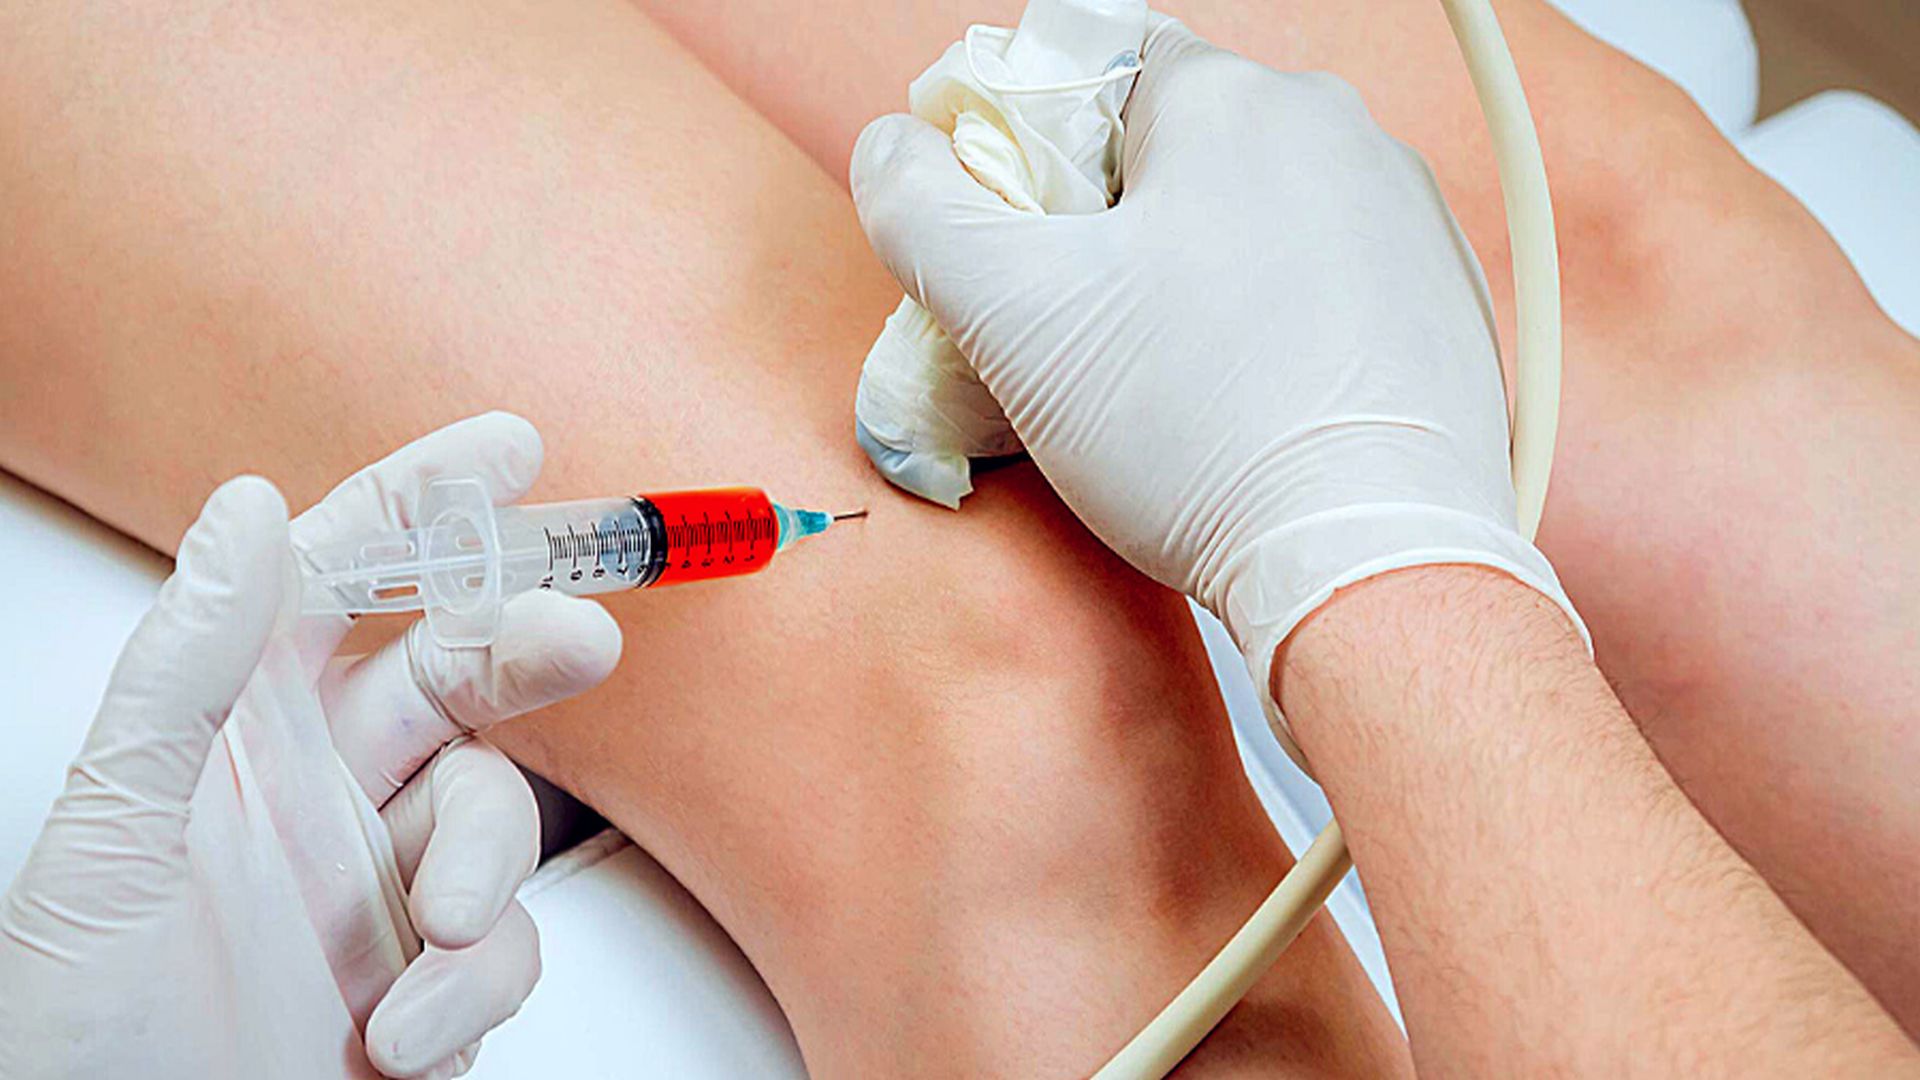

Kök hücre tedavisi

Yüzyılın tedavisi , ameliyatsız tedavi , Narkoz Yok , Ayni Gün Taburcu , %97 iyileşme garantisi , ülkemizde kök hücre tedavisini ilk yapan klinik biziz, dokuz yıldır bu tedaviyi başarı ile yapıyoruz.